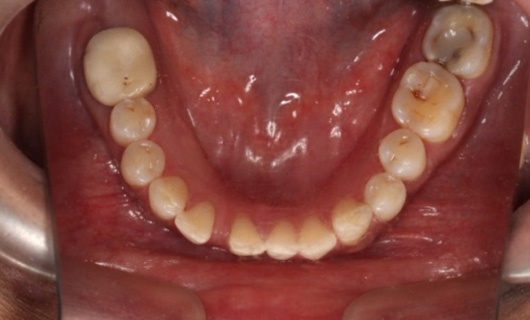

Like braces, Invisalign Braces straighten teeth by placing trays of special material over the teeth in their natural position. A gentle and constant force is used to move the teeth into the desired position without having to go through the hassle of metal wires and brackets. Through digital scanning, they are customized for every patient. Over time, they become a part of the body, since they are so snugly fitting. You are free to eat and drink anything since you will be removing all foods before every meal.